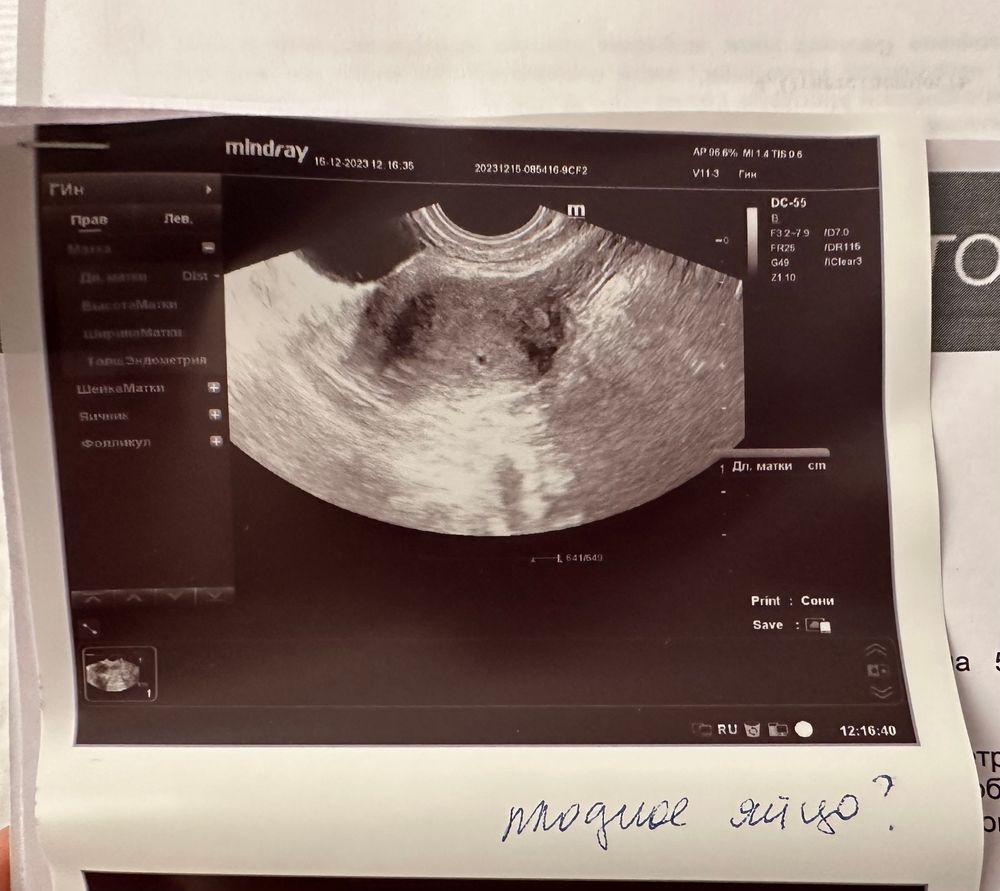

Неделю назад у меня было подозрение на ВБ, поехала в хорошую клинику, это было в вскр. Хгч был всего 100, но дело было после месячных уже. Поэтому, пя увидеть я не рассчитывала, но мне нужно было увидеть эндометрий, ЖТ, нет ли расширения в трубах и тд. Так вот первое узи у меня было как у вас, первая фаза цикла и барабанная дробь, якобы только что произошла овуляция. Я точно знала, что это невозможно. Уже позже, мне сделали второе узи, которое не имело ничего общего с первым. Я бы на вашем месте ориентировалась на второе, больше похоже на правду

Второе очевидно, нормальное узи. Весьма ваше пя. Растите в нужном месте ❤️